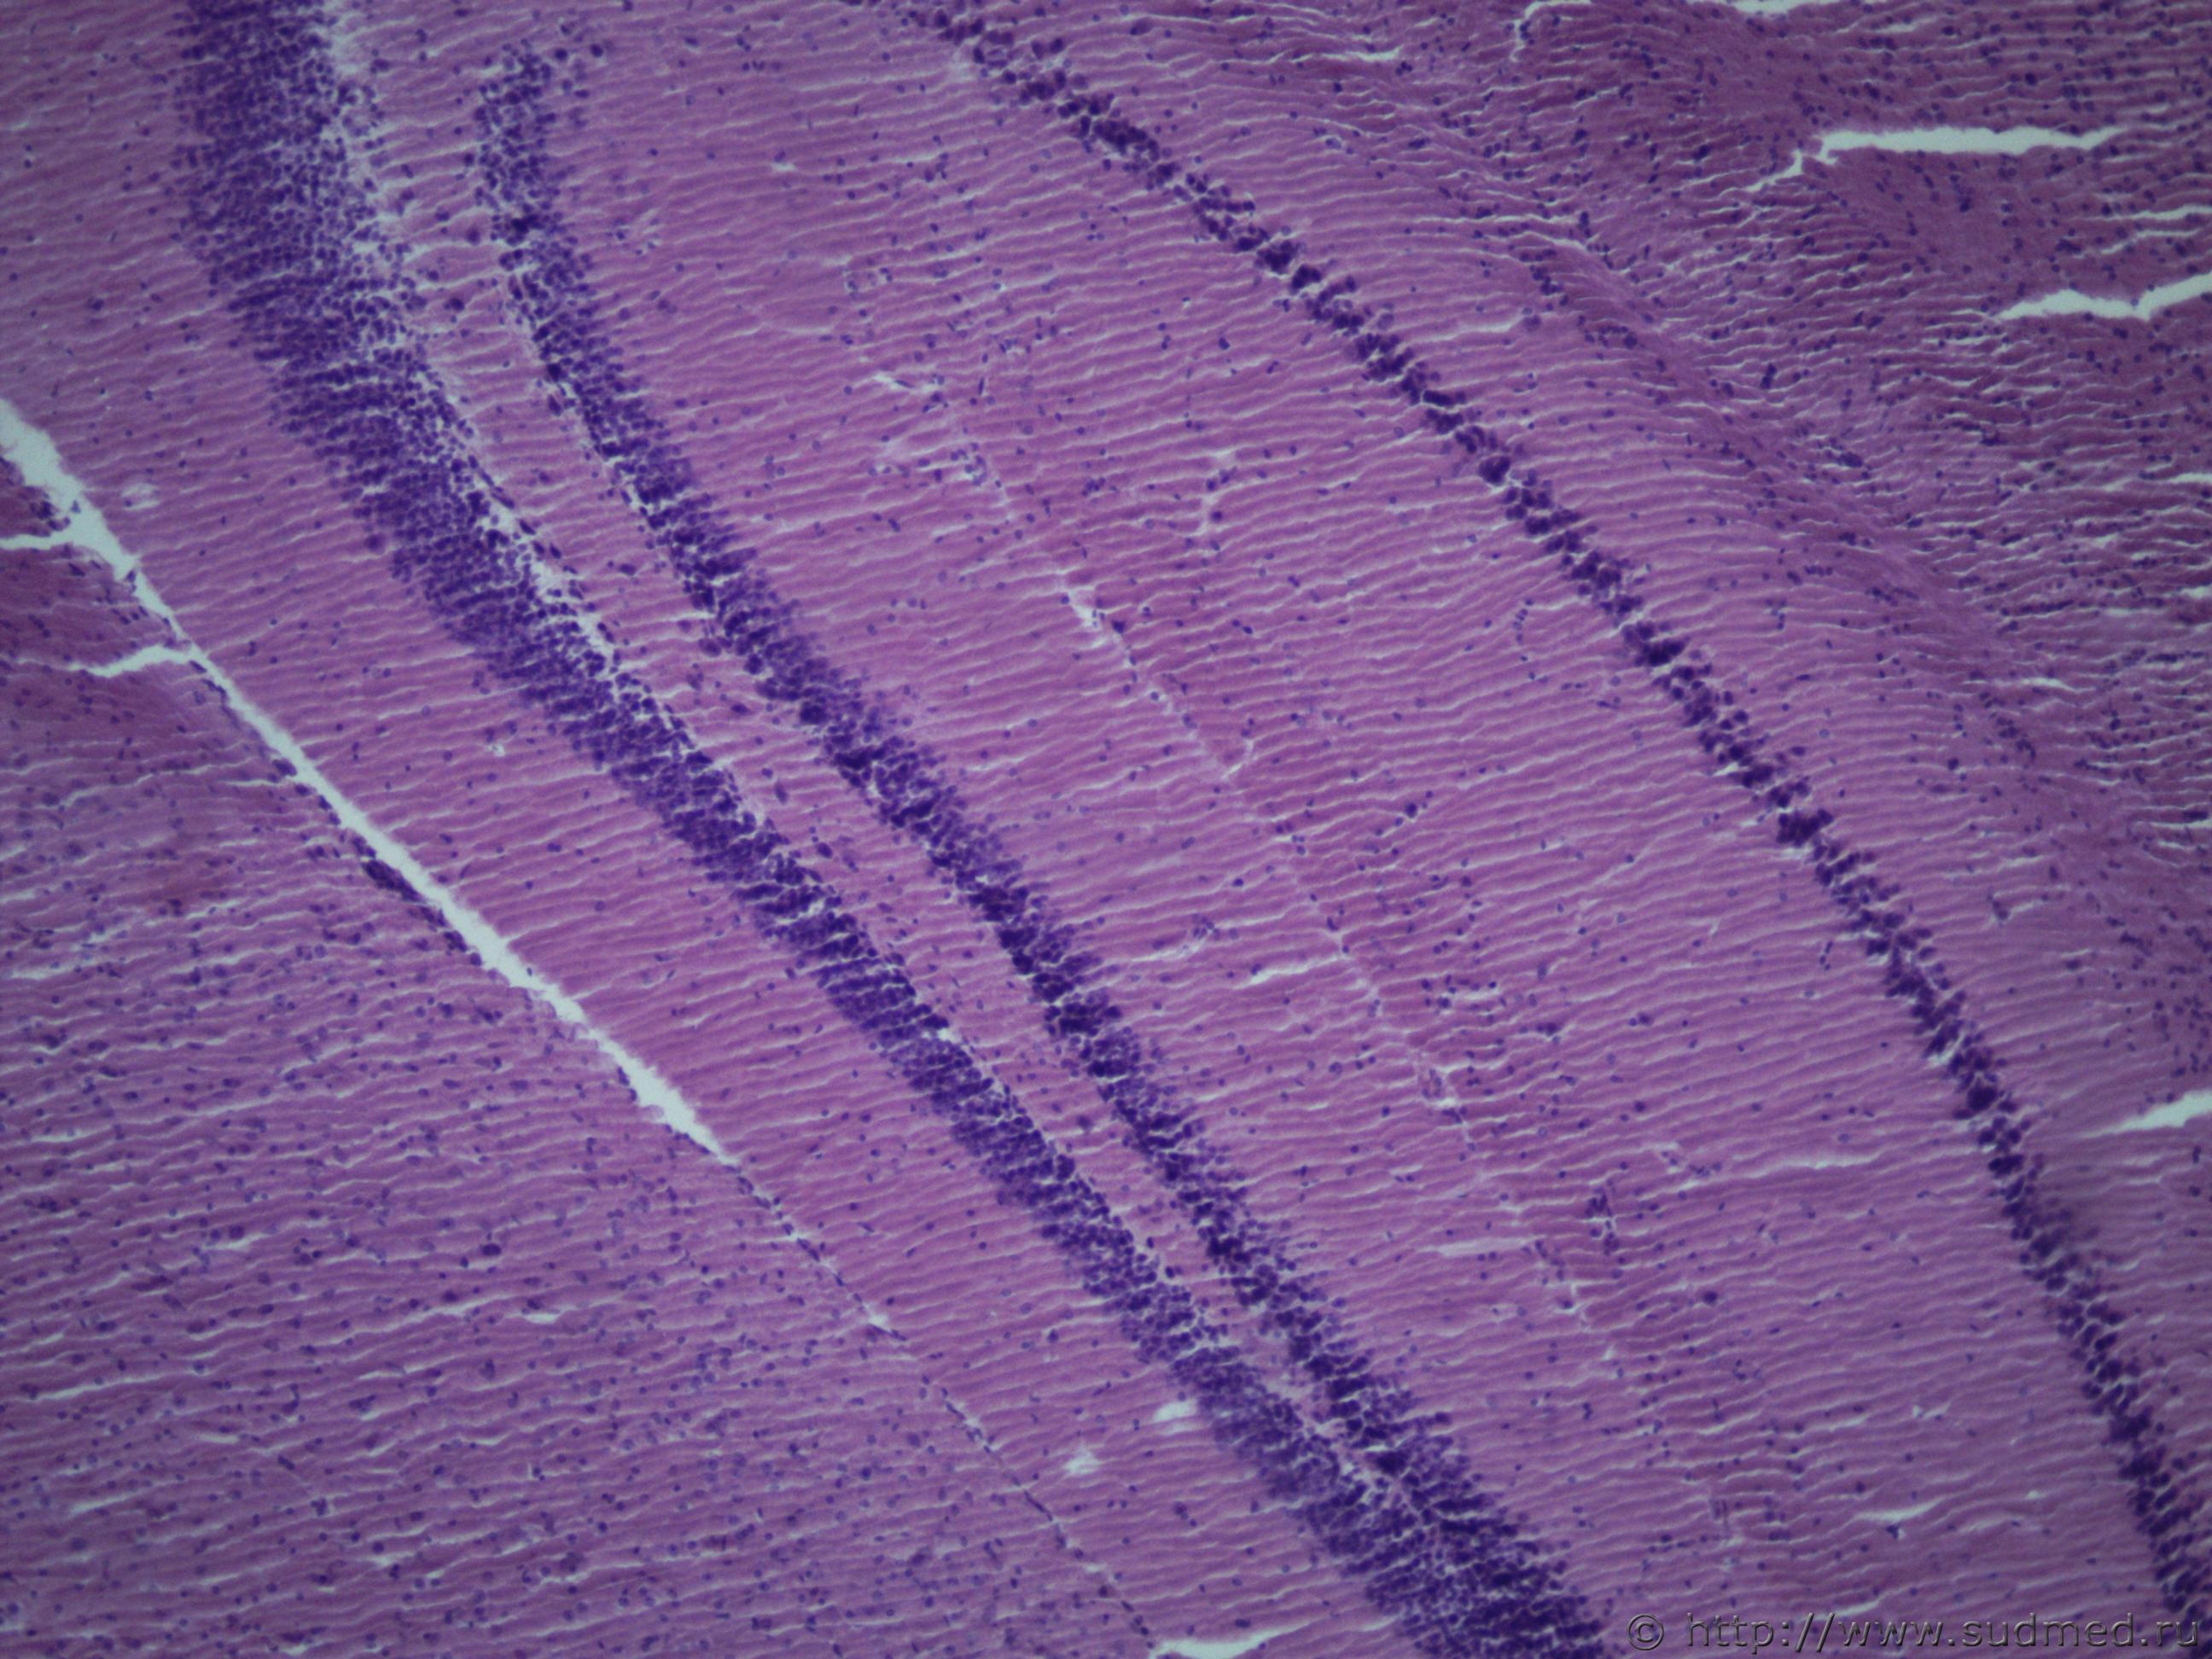

Ув. коллеги, подскажите похоже ли на олигодендроглиому в головном мозге крысы, область гиппокампа? Судебная медицина - Прикрепленное изображение Судебная медицина - Прикрепленное изображениеСудебная медицина - Прикрепленное изображениеСудебная медицина - Прикрепленное изображениеСудебная медицина - Прикрепленное изображение

А на что это может быть похоже, в норме область гиппокампа у крыс выглядит упорядоченно и более узкой полосой. Вот такСудебная медицина - Прикрепленное изображение

А это ,скорее всего,мозжечок.

Первое фото (сообщение №1), аналогично.

Мозжечка точно не может быть, так как я его при вырезки удалила, срез проходил в средней части головного мозга через височные доли. Мозжечок у крысы выглядит вот так Судебная медицина - Прикрепленное изображение , а это поперечный срез, области гиппокампа, в норме он выглядит вот такСудебная медицина - Прикрепленное изображение ув. в обоих фото х40